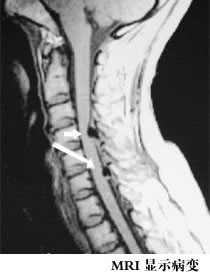

由於骨質增生症可發生於全身各部,臨床表現也就錯綜複雜,但治則總以補腎健骨、扶正祛邪、活血化瘀、軟堅消腫、疏通經絡等法為要。骨質增生症是人體衰老的一種正常退化現象,到了一定年齡每個人在活動較多而且負重較大的關節如頸椎、膝關節、腰椎等都會有不同程度的骨質增生,這些增生一般不會引起症狀,所以不能說一有這些部位的疼痛就拍片,發現有骨質增生就把它當成疼痛的原因,把它當成病,那就會產生很多很多的誤診誤治,如果增生的骨刺刺激到了局部組織或神經產生症狀的時候才叫骨質增生病,要結合病人的症狀和體徵規律特點來綜合診斷。